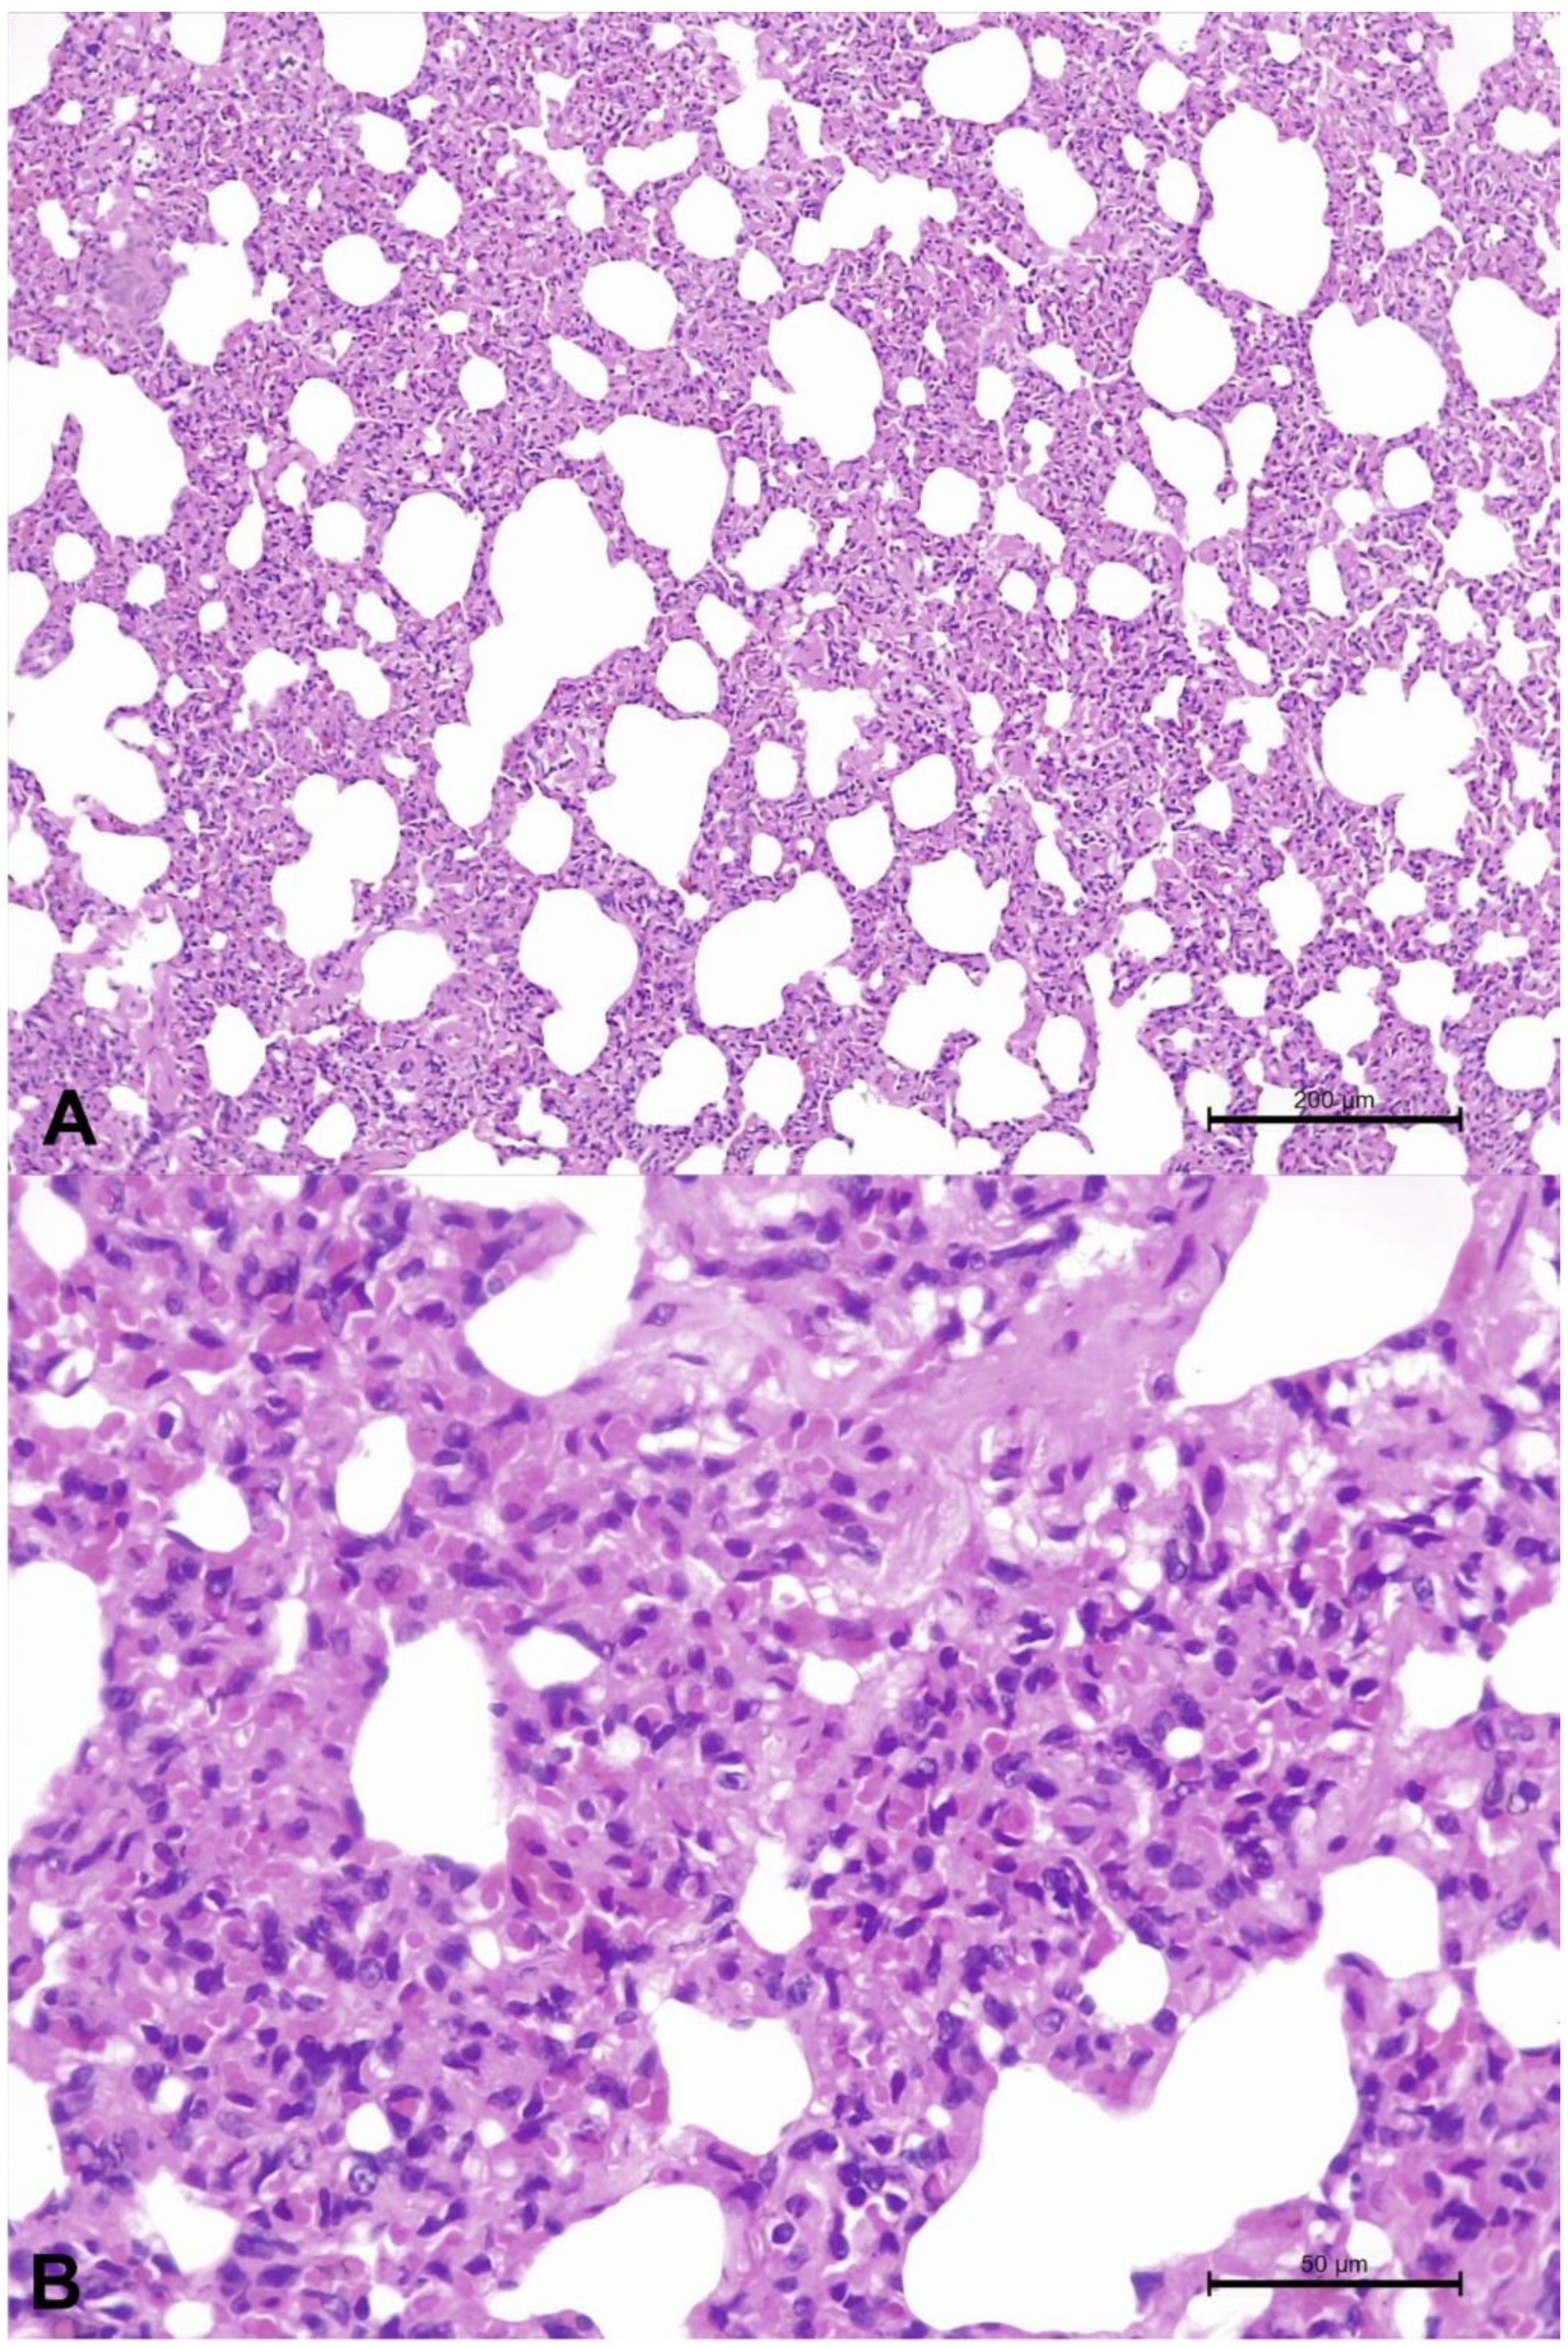

2.5. Clinical, Gross, Histopathologic, and Immunohistochemical Findings